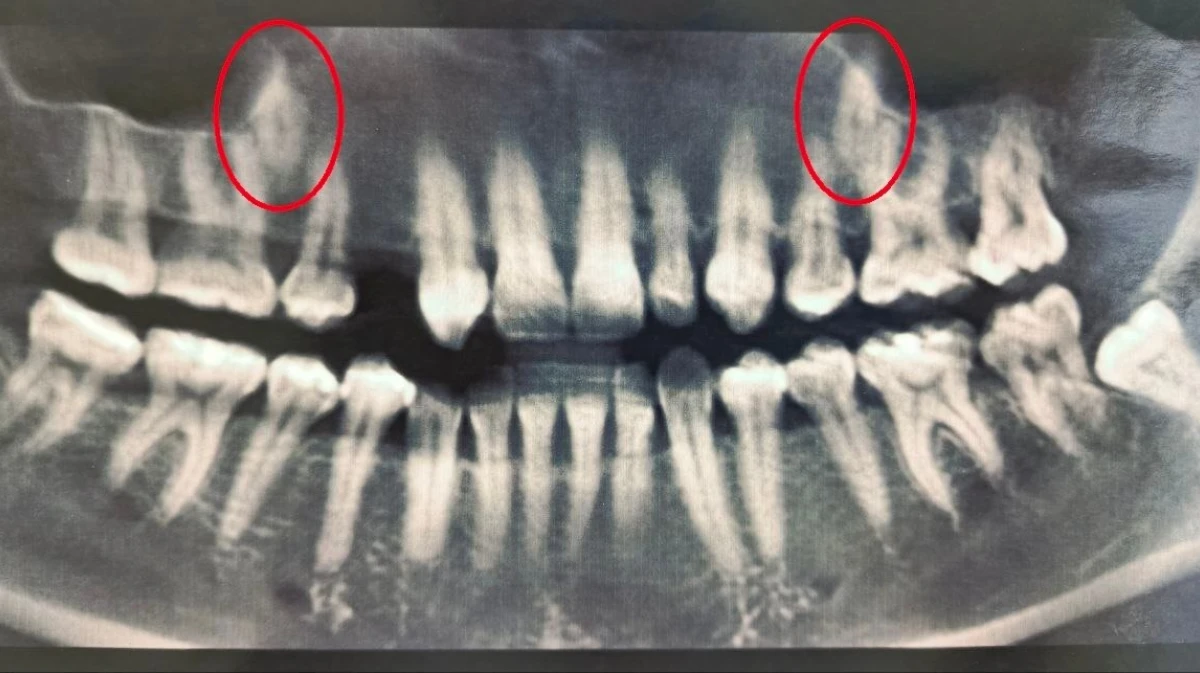

В 2023 году в областную стоматологическую клинику обратилась 38-летняя женщина с двумя непрорезавшимися зубами в основном ряду. Стоматологи обследовали пациентку и провели ей компьютерную томографию. Выяснилось, что один из зубов у женщины полностью отсутствовал, а второй был намного меньше нормы. Тогда врачи решили вмешаться и переместить непрорезавшиеся зубы в ряд. Об этом сообщили в региональном министерстве здравоохранения в пятницу, 30 января.

Стоматологи установили пациентке брекеты, которые та носила на протяжении полутора лет, создавая место для новых зубов. После этого врачи хирургически раскрыли коронки непрорезавшихся зубов и зафиксировали ортодонтические кнопки для их вытяжения. На данный момент благодаря специальному оборудованию один из зубов полностью вышел из костной ткани, а второй успешно прорезается.

В региональном минздраве отметили, что при правильном сочетании диагностических методик, врачебного опыта и соблюдения всех медицинских рекомендаций можно вылечить даже аномалии зубочелюстной системы.